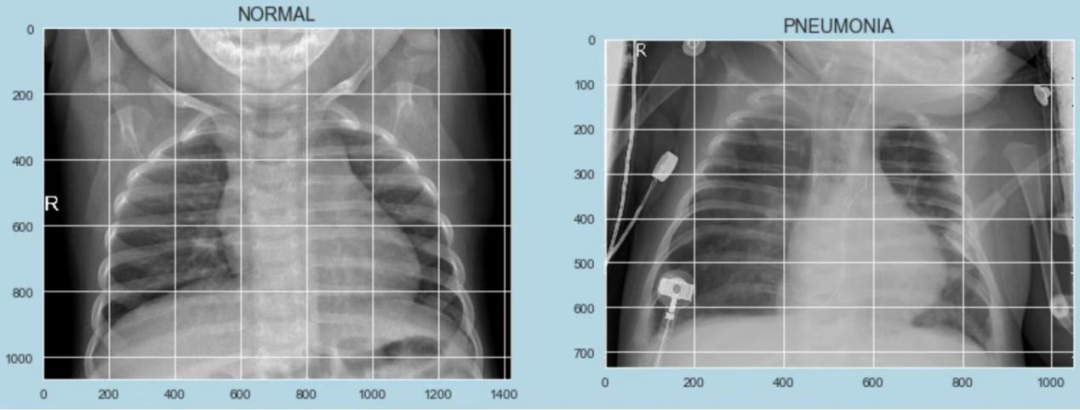

医学影像是医生判断疾病的一个重要手段,放射科、病理科等擅长读图的医生增长率和诊断效率急需提升,成为很多医疗机构的心病。医疗领域深度学习团队Airdoc,目前已经掌握了世界领先的图像识别能力,结合数学、医学知识和深度学习深度学习算法后,在人类医学专家的帮助下,在心血管、肿瘤、神内、五官等领域建立了多个精准深度学习医学辅助诊断模型,取得了良好的进展。

以糖尿病性视网膜病变判断为例,国际上将糖尿病视网膜病变从正常到严重分成了5类。Airdoc在眼科专家的帮助下,通过让深度学习算法学习远超人类医生一生接诊量的的患者眼底照片,训练了一个检测糖尿病视网膜病变的深度神经网络,该算法在有明显症状和无明显症状二分方面准确性与三甲资深眼科医生持平,对眼科专家不足的地域和广大基层医疗机构开展筛查具有现实意义。同时,该算法在眼底照片国际标准5分类方面准确性也不逊于专业眼科医生。类似的高可靠医学影像深度学习算法,还被Airdoc引入到DR、CT、核磁与病理影像辅助诊断中,这些深度学习算法在我国推进家庭医生签约和增强基层医疗机构服务能力等领域都有广阔应用。